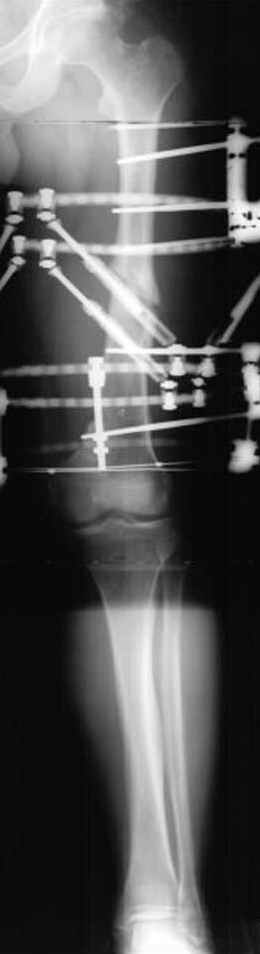

Несколько снимков из моей коллекции, чтобы разьяснить, почему мы до сих пор делаем различные варианты остеотомии.

На рисунке N1 предоперационный план лечения ложного сустава шейки бедра- линия ложного сустава, угол и направление введения импланта, клиновидная остеотомия в градусах и миллиметрах, второй снимок после коррекции, расчет, на сколько удлиняется конечность и размеры импланта;

N3 рисунок окончательный снимок, после операции моя рентгенограмма должен выглядеть примерно как эта картина. На N4 снимке клин перед удалением; N5 послеоперации 3 нед.; N6 окончательная рентгенограмма.

(доложен в Ст. Петербурге 2003 и в Москве 2004)

Отправитель: Djoldas Kuldjanov 23 Ноябрь 2004, 18:21

пластическая модель; и коррекция бедра аппаратом Илизарова.

Имею другие снимки тоже, получится как отчет о моей работе.